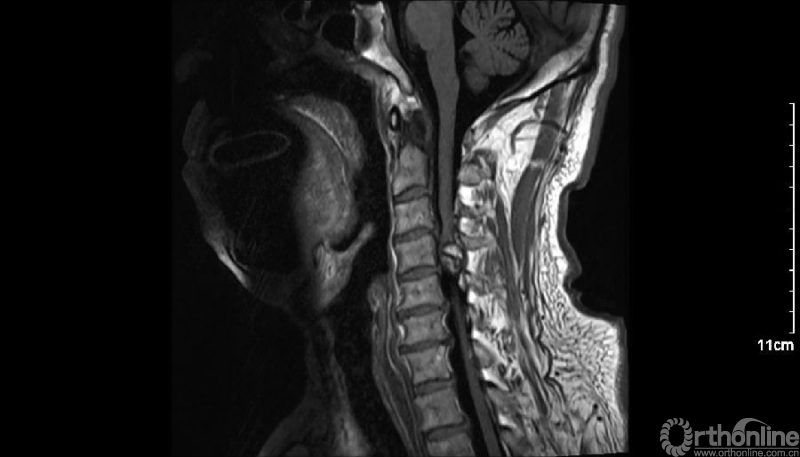

入院查体患者四肢肌张力高,双侧hoffman阳性。CT及MRI检查提示C4/5左侧关节突内缘有一巨大骨块(15mm*16mm),相应节段椎管严重狭窄。椎管内骨块的前端还有一游离骨块。

影像学资料